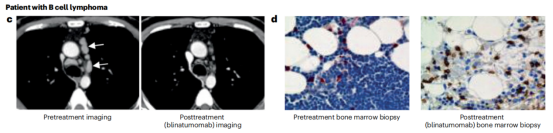

Blinatumomab由双特异性抗体所需的最小元素组成;一种靶向癌症的scFv(抗CD19)。Blinatumomab通过抗CD19scFv作用于B细胞,同时通过抗CD3scFv连接和激活T细胞,导致B细胞死亡。Blinatumomab在一系列B细胞恶性肿瘤中显示出活性,并被批准用于治疗B细胞前体急性淋巴细胞白血病(B-ALL)。